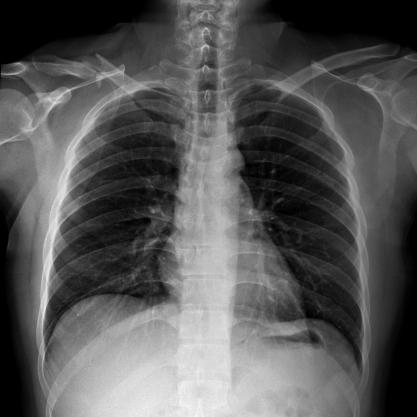

滿足不同身高的受檢者快速地進行胸片的靜態(tài)及動態(tài)檢查,適合大規(guī)模體檢。

SID可拉伸至1.8米,滿足標準胸片、職業(yè)性塵肺病檢查等特殊需求。